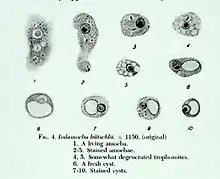

Trophozoite

The trophozoites are 9–14 micrometres in diameter. Trophozoites are one of the two forms of I. buetschlii. This form has a pseudopodia for locomotion. The pseudopodia is short and blunt. It moves in a slow manner. The trophozoite has a single nucleus, prominent for nuclear endosome and many cytoplasmic vacuoles. The ectoplasm and the granular endoplasm are often hard to distinguish. The nucleus is fairly large and vesicular, containing a large endosome, surrounding by light staining granules about midway between it and the nuclear membrane. Achromatic strands stretch between the endosome and nuclear membrane without any peripheral granules. Food vacuoles are commonly filled with bacteria and yeast. Trophozoites are often identified by a stool smear, found in loose stools.[3][4]

Cyst

The cysts are 8–10 micrometres in diameter, with a thick wall and a large glycogen vacuole that stains darkly with iodine. Usually harmless, it may cause amebiasis in immunologically compromised individuals.

[5][6] As the second form of I. butschlii, cysts have an oval shaped- single nucleus with a prominent nuclear endosome. This form is also large, single, glycogen-filled vacuole called iodinophilous vacuole (glycogen stains with iodine). Cysts are the infective stage of I. buetschlii. Unlike trophozoites, cysts are often found in formed stools.[4]